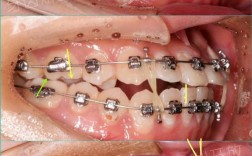

- 阶段判断: 如果你的上颌现在戴着的是一根细的、银色或蓝色的、有点弹性的圆丝,那么你很可能处于这个第一阶段或早期阶段。

- 阶段判断: 如果你的上颌现在戴着的是一根方形的、颜色可能是银色(不锈钢)或蓝色/金色(镍钛)的丝,并且医生可能在关注你牙齿之间的缝隙(特别是拔牙位置),那么你很可能处于这个第二阶段或中期阶段。

- 阶段判断: 如果你的上颌戴着的是一根非常细的方丝或圆丝,或者医生在用精细的工具调整你的牙齿,并且告诉你“快好了”或“在精细调整了”,那么你很可能处于这个第三阶段或后期阶段。

- 看丝的形态: 是圆丝还是方丝?粗还是细?

- 看丝的材质/颜色: 银色(不锈钢)?蓝色/金色(镍钛)?